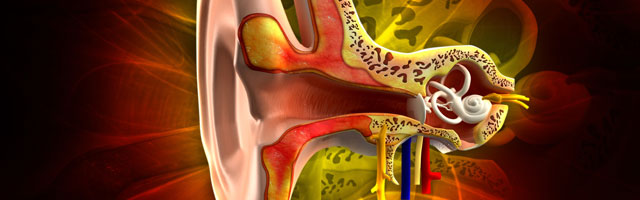

These kinds of problems can occur with vestibular disorders and can be severe and debilitating. Our Vestibular system helps us to maintain balance and equilibrium. When disorders of the vestibular system occur, organs of the inner ear are disrupted and we experience vertigo (often referred to as dizziness) and balance problems.

Many vestibular disorders can be effectively treated with physical therapy. The most common vestibular disorders treated by physical therapy are BPPV (Benign Paroxysmal Position Vertigo), which is a disorder of the inner ear canals, and Hypo-functioning, (under functioning) of one side of the vestibular system which can result after an infection or virus of the inner ear.

Hypo-functioning of the vestibular system often occurs with a virus or infection of the inner ear such as Labyrinthitis or Vestibular Neuritis. Physical therapy is highly effective in addressing each of these problems as well as many others listed below.